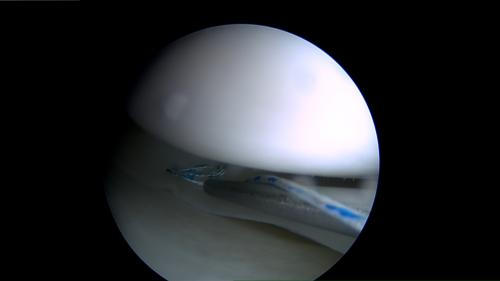

Arthroskopie =

Gelenkspiegelung

Arthroskopie = Gelenkspiegelung

Diagnostische und

resezierende

Arthroskopien und

transarthroskop.

Meniskusresektion

und -refixation.